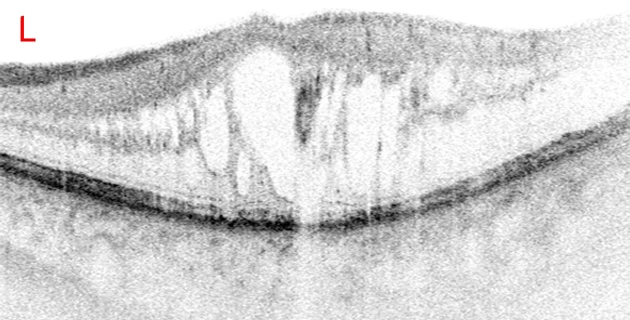

Mittels Fluoreszenzangiographie und optischer Cohärenztomographie (OCT) lassen sich die einzelnen Formen darstellen und klassifizieren. Die Regulierung eines erhöhten Blutdruckes und die Behandlung von Risikofaktoren wirken sich günstig auf die Prognose aus.

Neben fokaler, sektorieller oder panretinaler Lasertherapie ist die intravitreale operative Medikamentengabe (IVOM) bei einem Makulaödem Therapie der Wahl.